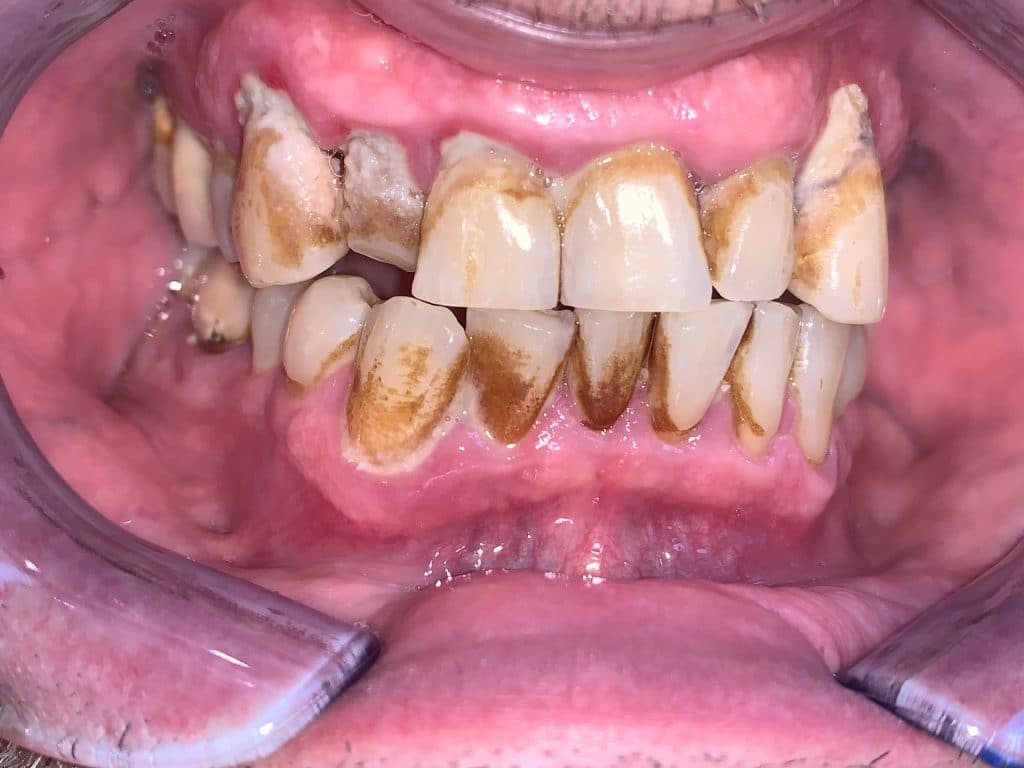

Performing the complete instrumentation

supragingival and subgingival with ultrasonic and / or manual instruments in one

single session or in two sessions at most performed over 2 days